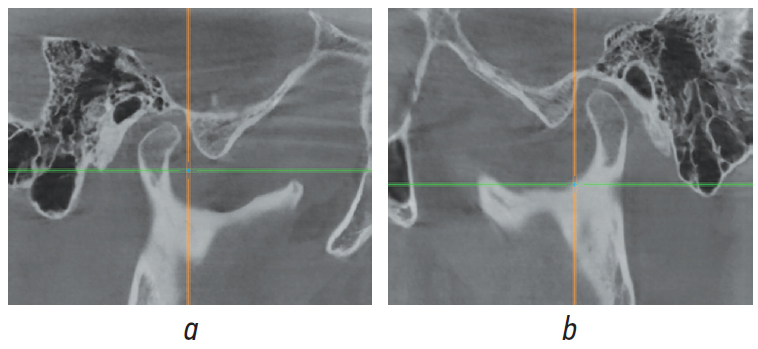

Обоим пациентам предложен аппаратурно-хирургический план лечения, подразумевающий санацию полости рта, декомпенсацию соотношения зубных рядов при помощи брекет-системы, двучелюстную/одночелюстную операцию с перемещением обеих челюстей/нижней челюсти вперед. Анализ КЛКТ височно-нижнечелюстного сустава (ВНЧС) пациента Ч. (рис. 8 а, b) позволил рассматривать в качестве альтернативного плана коррекцию соотношения зубных рядов в сагиттальном и вертикальном направлениях при помощи аппарата Гербста [2–4]. Анализ КЛКТ ВНЧС пациентки Ж. (рис. 9 а, b) выявил переднее положение головки нижней челюсти справа и ее резорбцию слева, что позволило обосновать план лечения с применением ортогнатической операции и эндопротезированием с целью коррекции признаков ЗЧЛА в сагиттальном, вертикальном и трансверзальном направлениях [5] (рис. 10).

Рис. 8. Сагиттальный срез конусно-лучевой компьютерной томографии височно-нижнечелюстного сустава пациента Ч. справа (а) и слева (b)

Fig. 8. Sagittal slice of cone-beam computed tomography of the temporomandibular joint of patient Ch. on the right (a) and left (b)